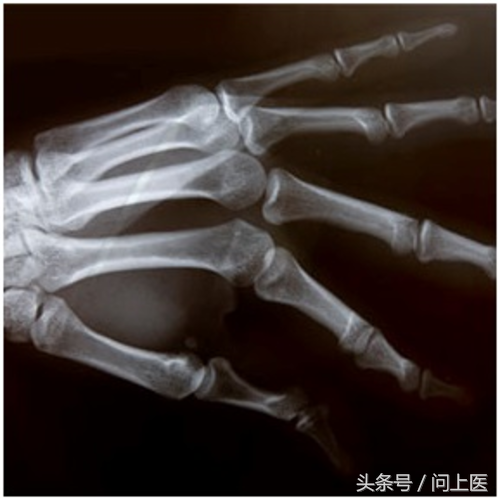

医生会仔细检查验血结果。如果血液中含有类风湿因子抗体,并伴有全身关节疼痛的症状,则很可能患有类风湿性关节炎。多处关节都可能发生疼痛,常见的有腕关节、手部关节、肘关节、肩关节、踝关节、膝关节。 X光检查也可以查看关节损坏情况,并帮助诊断关节炎。医生还可能要求定期进行X光检查,以诊断病情发展。